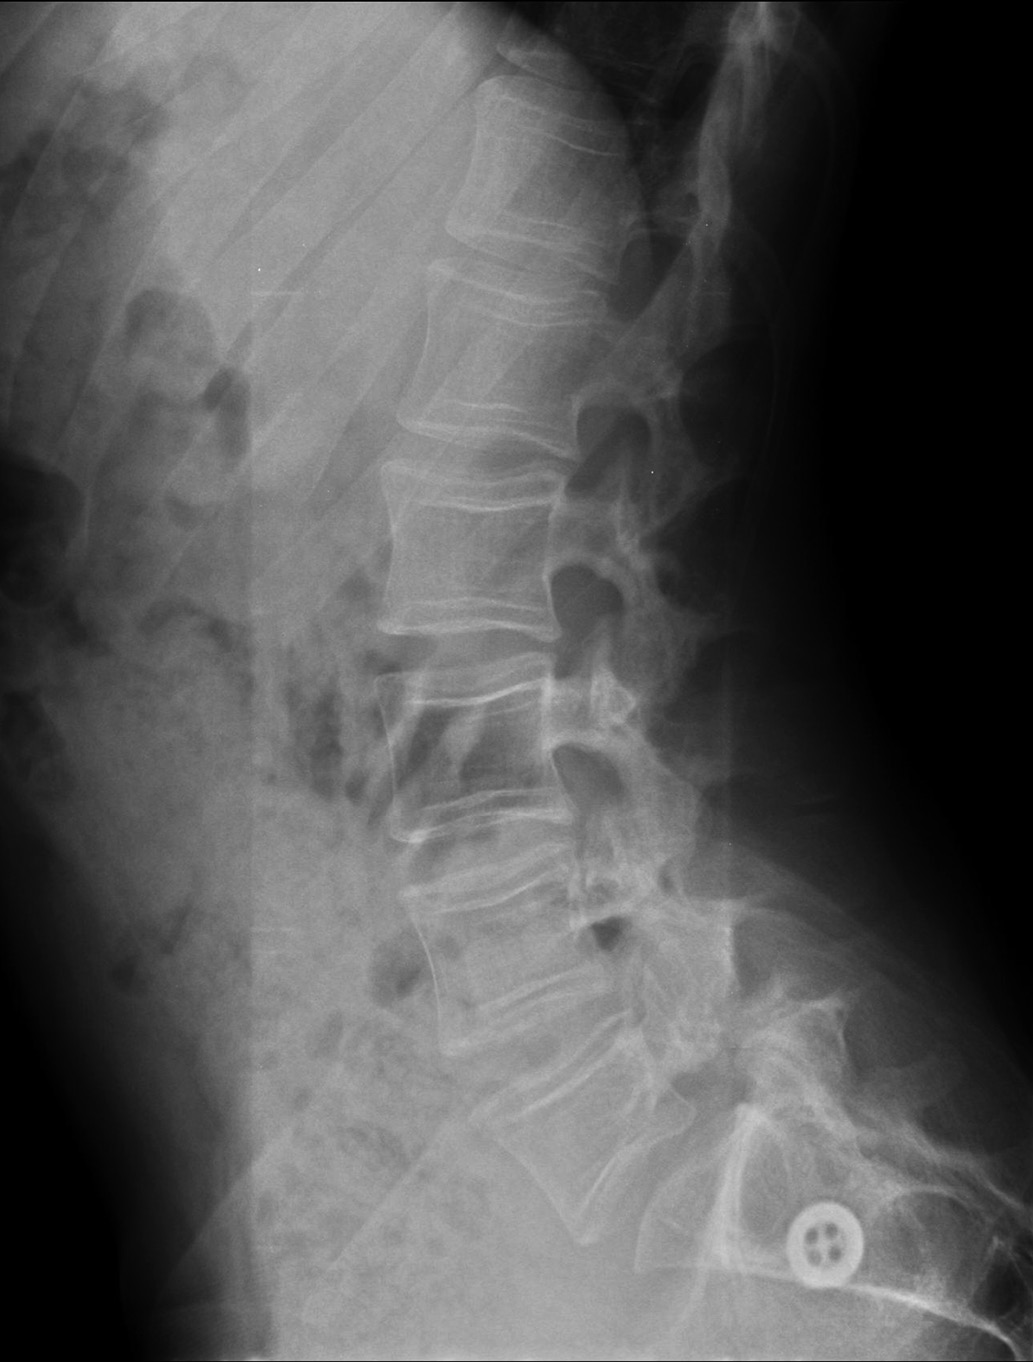

Проведена боковая рентгенография грудного и поясничного отделов позвоночника, компрессионных переломов тел позвонков не выявлено (рис. 3).

Рисунок 3. Боковая рентгенография грудного и поясничного отделов позвоночника пациента А.